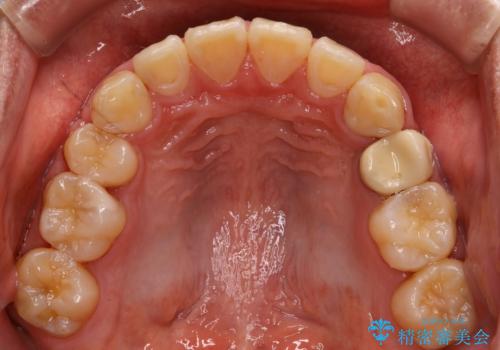

- 上顎前歯の突出感と下顎前歯のガタつきが主訴で来院されました。

出っ歯とガタつきの改善を行うには抜歯が必要と診断し、上下左右第一小臼歯を抜歯する計画を立てました。

抜歯する事で歯の移動量が大きいことからワイヤー表側矯正装置で治療を行うことになりました。

今回のような歯の移動量が大きい場合、インビザライン治療では歯が傾いてしまう場合があります。

ワイヤー治療では歯の傾きを抑えながら大きい距離の移動が可能で、かみ合わせが深くなるリスクも少ないです。